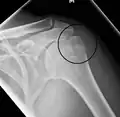

A fracture of the greater tuberosity as seen on AP X ray

A fracture of the greater tuberosity of the humerus

Fracture of the greater tuberosity of the humerus